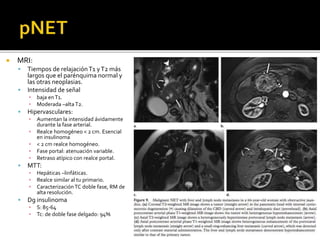

 MRI:

 Tiempos de relajaciónT1 yT2 más

largos que el parénquima normal y

las otras neoplasias.

 Intensidad de señal

▪ baja enT1.

▪ Moderada –altaT2.

 Hipervasculares:

▪ Aumentan la intensidad ávidamente

durante la fase arterial.

▪ Realce homogéneo < 2 cm. Esencial

en insulinoma

▪ < 2 cm realce homogéneo.

▪ Fase portal: atenuación variable.

▪ Retraso atípico con realce portal.

 MTT:

▪ Hepáticas –linfáticas.

▪ Realce similar al tu primario.

▪ Caracterización TC doble fase, RM de

alta resolución.

 Dg insulinoma

▪ S: 85-64

▪ Tc: de doble fase delgado: 94%